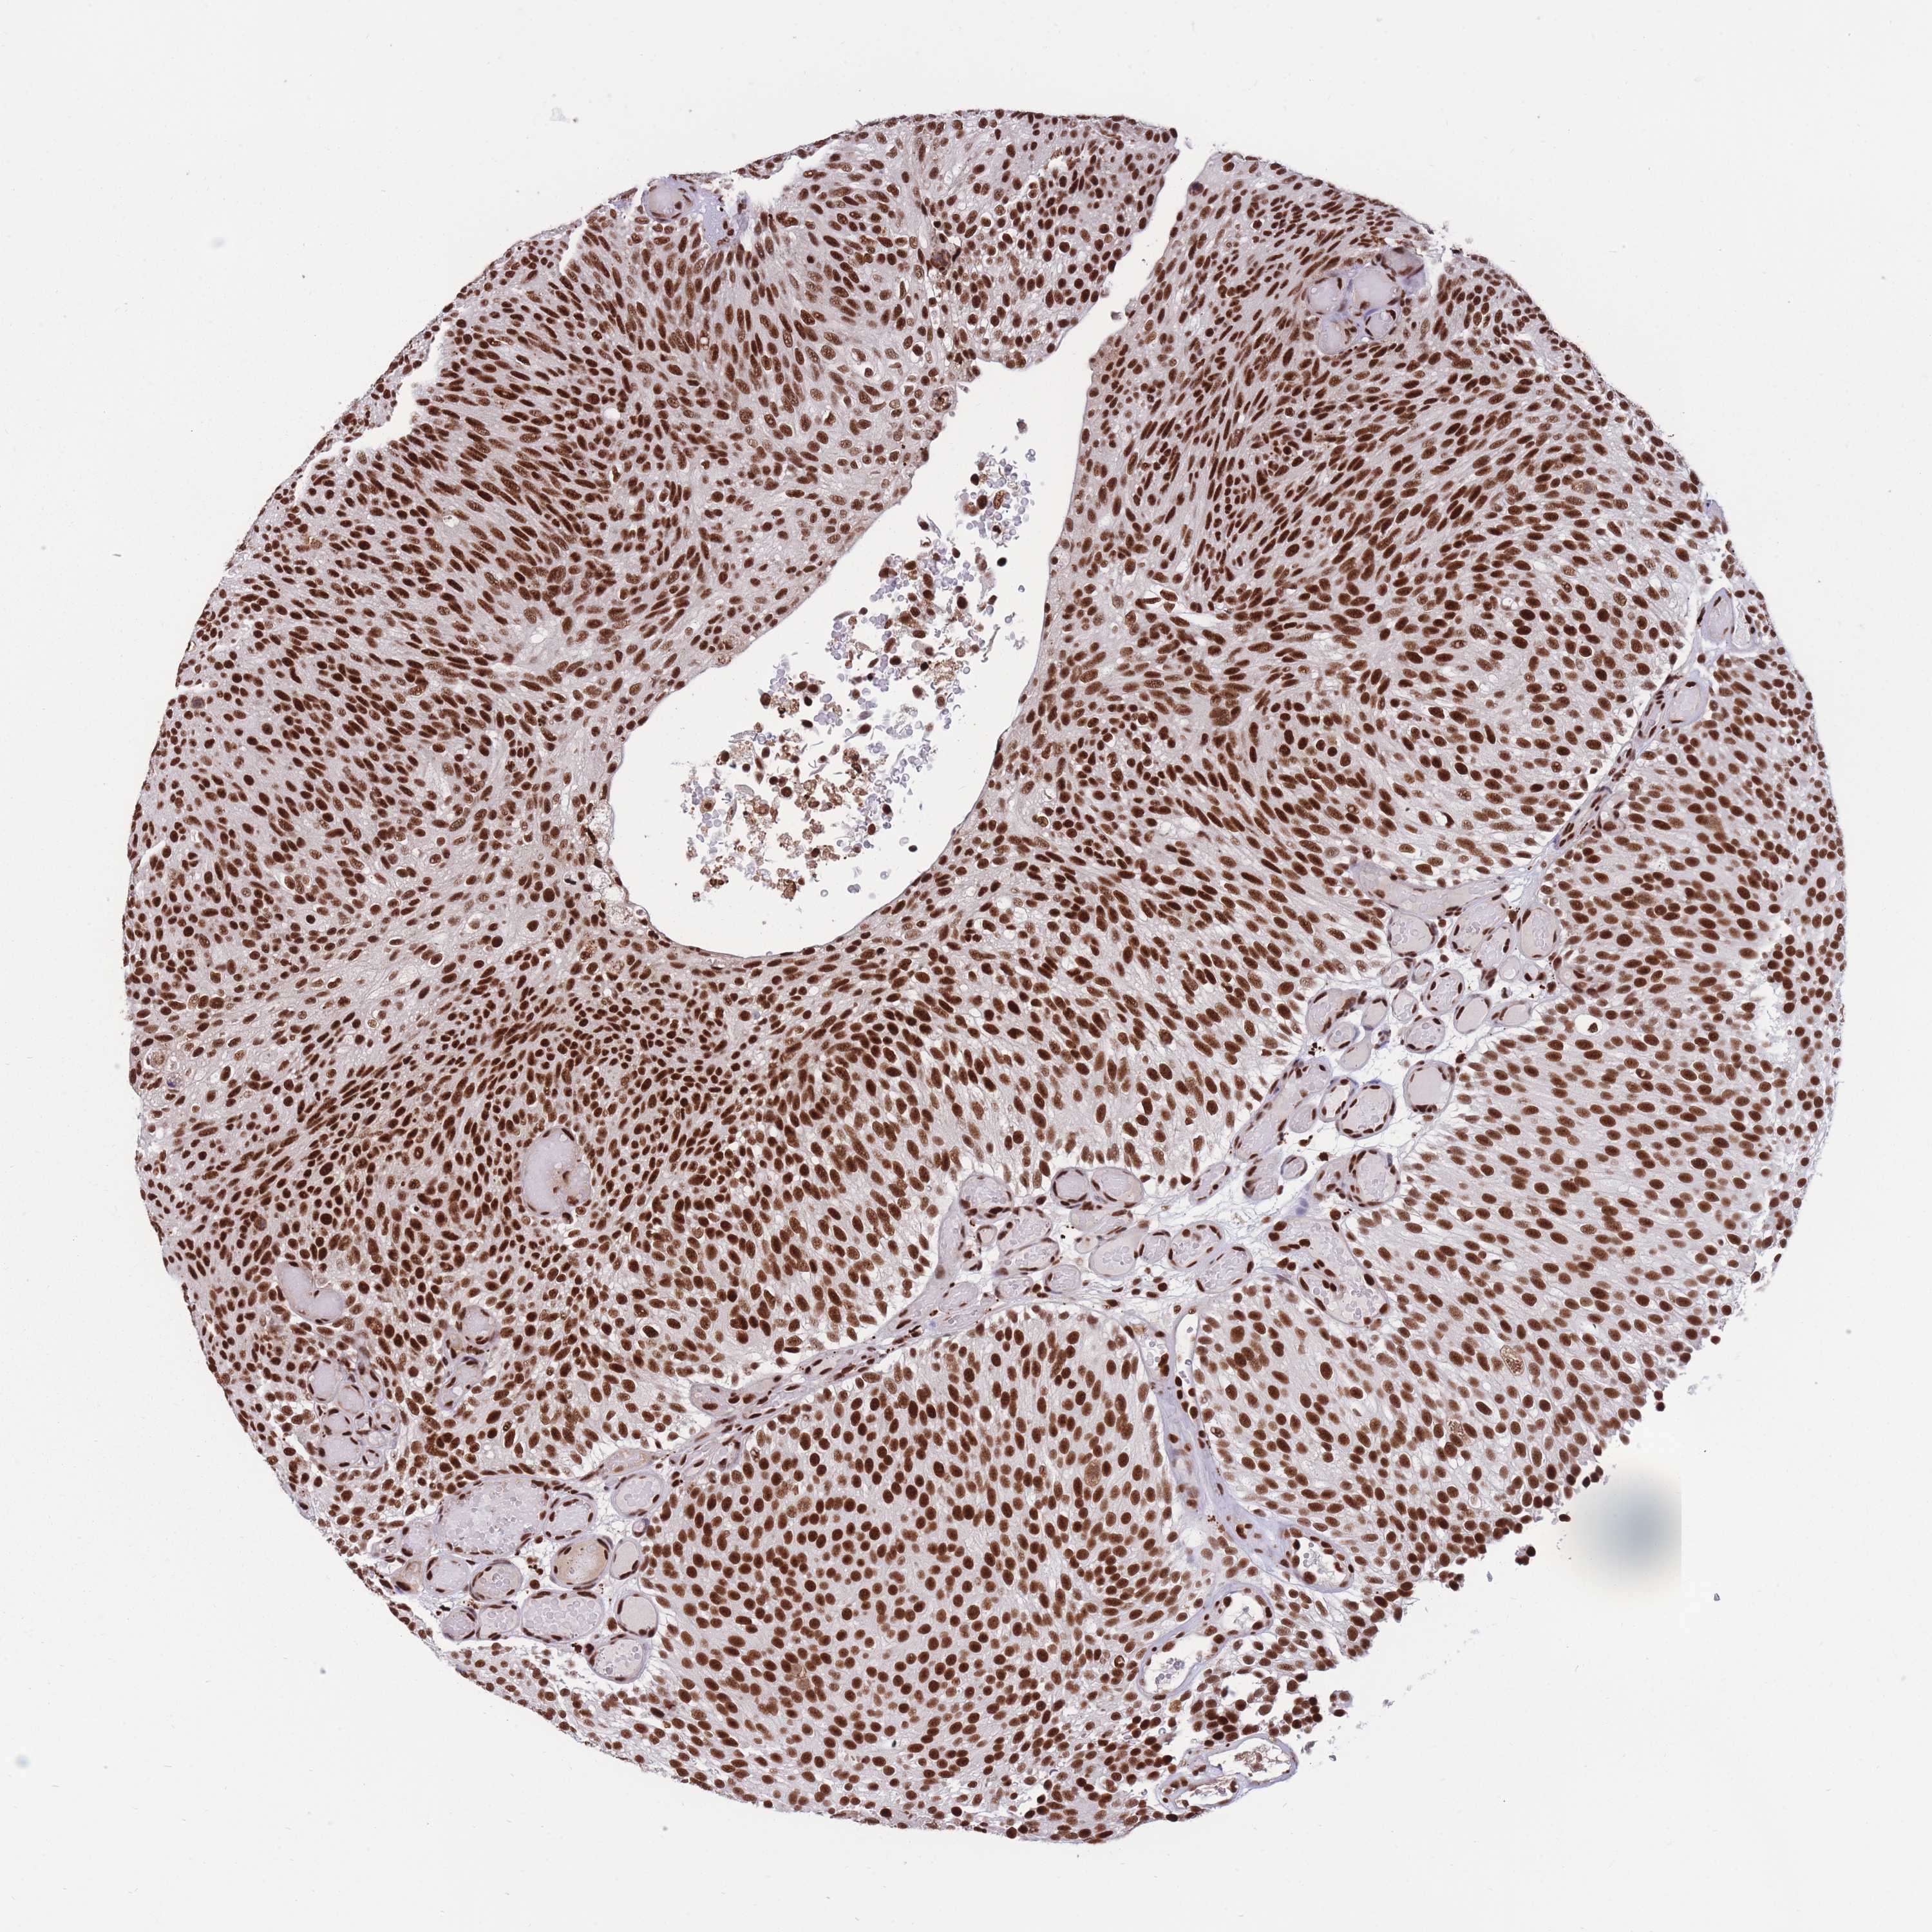

UROTHELIAL CANCER - Protein expressioni

A mouse-over function shows sample information and annotation data. Click on an image to view it in a full screen mode. Samples can be filtered based on level of antibody staining by selecting one or several of the following categories: high, medium, low and not detected. The assay and annotation is described here.

Note that samples used for immunohistochemistry by the Human Protein Atlas do not correspond to samples in the TCGA dataset.

Antibody stainingi

Antibody staining in the annotated cell types in the current human tissue is reported as not detected, low, medium, or high, based on conventional immunohistochemistry profiling in selected tissues. This score is based on the combination of the staining intensity and fraction of stained cells.

Each image is clickable and will lead to virtual microscopy that enables deeper exploration of all samples and also displays staining intensity scores, fraction scores and subcellular localization as well as patient and tissue information for each sample.

Antibody HPA038051

Antibody HPA059070

Antibody CAB012448

Staining

High

Medium

Low

Not detected

Intensity

Strong

Moderate

Weak

Negative

Quantity

>75%

75%-25%

<25%

None

Location

Nuclear

Cytoplasmic/membranous

Cytoplasmic/membranous,nuclear

Urothelial carcinoma, High grade

Urothelial carcinoma, Low grade

Urothelial carcinoma, NOS